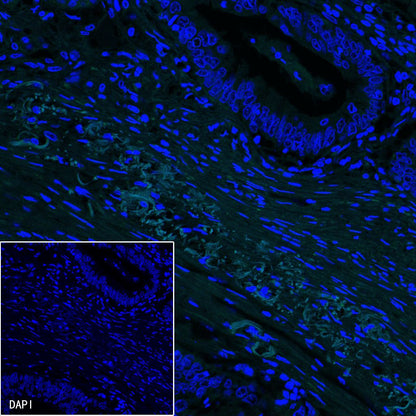

Immunofluorescence

IF shows positive staining in paraffin-embedded human colon cancer. Anti-PDGFRA+PDGFRB antibody was used at 1/100 dilution (Green) and incubated overnight at 4°C. Goat polyclonal Antibody to Rabbit IgG - H&L (Alexa Fluor® 488) was used as secondary antibody at 1/1000 dilution. Counterstained with DAPI (Blue). Heat mediated antigen retrieval with EDTA buffer pH9.0 was performed before commencing with IF staining protocol.